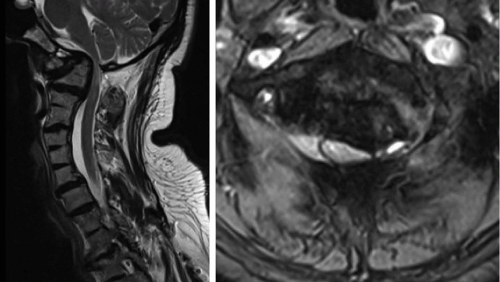

A 51-year-old male presented to us with numerous craniocervical developmental abnormalities and severe cervical myelopathy because of occipitocervical assimilation, basilar invagination, and C1-2 instability. He was admitted for preoperative cervical traction, which provided partial reduction of the basilar invagination (Figures 8-1 and 8-2).

Figure 8-3 ▪ Sagittal T2-weighted MR image, demonstrating severe cord compression with atrophy and myelomalacia at the occipitocervical junction.